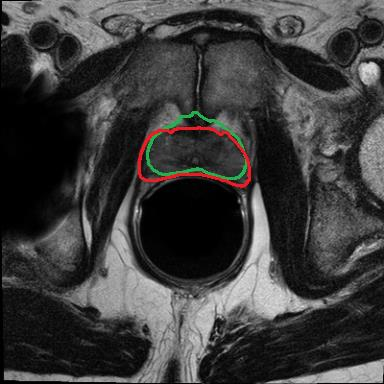

Modern deep neural networks struggle to transfer knowledge and generalize across diverse domains when deployed to real-world applications. Currently, domain generalization (DG) is introduced to learn a universal representation from multiple domains to improve the network generalization ability on unseen domains. However, previous DG methods only focus on the data-level consistency scheme without considering the synergistic regularization among different consistency schemes. In this paper, we present a novel Hierarchical Consistency framework for Domain Generalization (HCDG) by integrating Extrinsic Consistency and Intrinsic Consistency synergistically. Particularly, for the Extrinsic Consistency, we leverage the knowledge across multiple source domains to enforce data-level consistency. To better enhance such consistency, we design a novel Amplitude Gaussian-mixing strategy into Fourier-based data augmentation called DomainUp. For the Intrinsic Consistency, we perform task-level consistency for the same instance under the dual-task scenario. We evaluate the proposed HCDG framework on two medical image segmentation tasks, i.e., optic cup/disc segmentation on fundus images and prostate MRI segmentation. Extensive experimental results manifest the effectiveness and versatility of our HCDG framework.